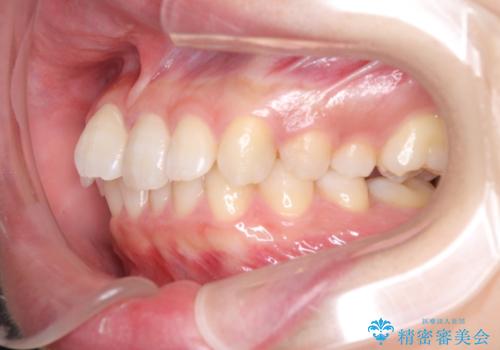

最難関と思われたシザーズバイトは比較的短期間で解消されました。

しかし、治療中に2度の出産を経験され、治療期間は長くなってしまいましたが、咬みやすく、清掃しやすい歯列を獲得することができました。